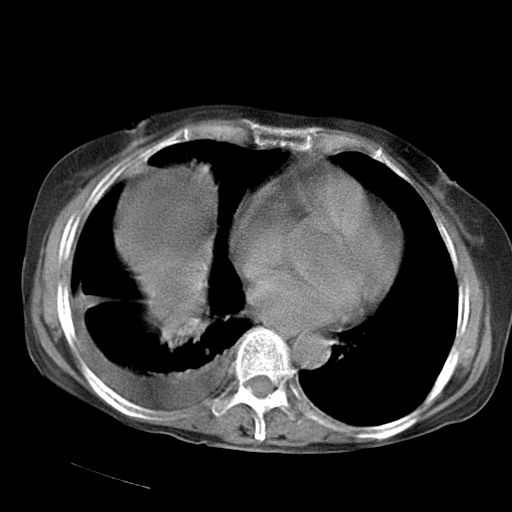

以下是引用dyqct在2006-12-7 21:08:00的发言:[br]考虑:1、肝内外胆管多发性结石伴肝左叶外侧段肝萎缩;[br] 2、右膈下多发脓肿;[br] 3、右侧少量胸腔积液、斜裂积液;[br] 4、左肾囊肿。

以下是引用拾荒者在2006-12-7 21:44:00的发言:[br]肝内外胆管多发结石,右膈下多发脓肿,右胸膜腔及叶间裂积液,左肾囊肿。[br] [br]